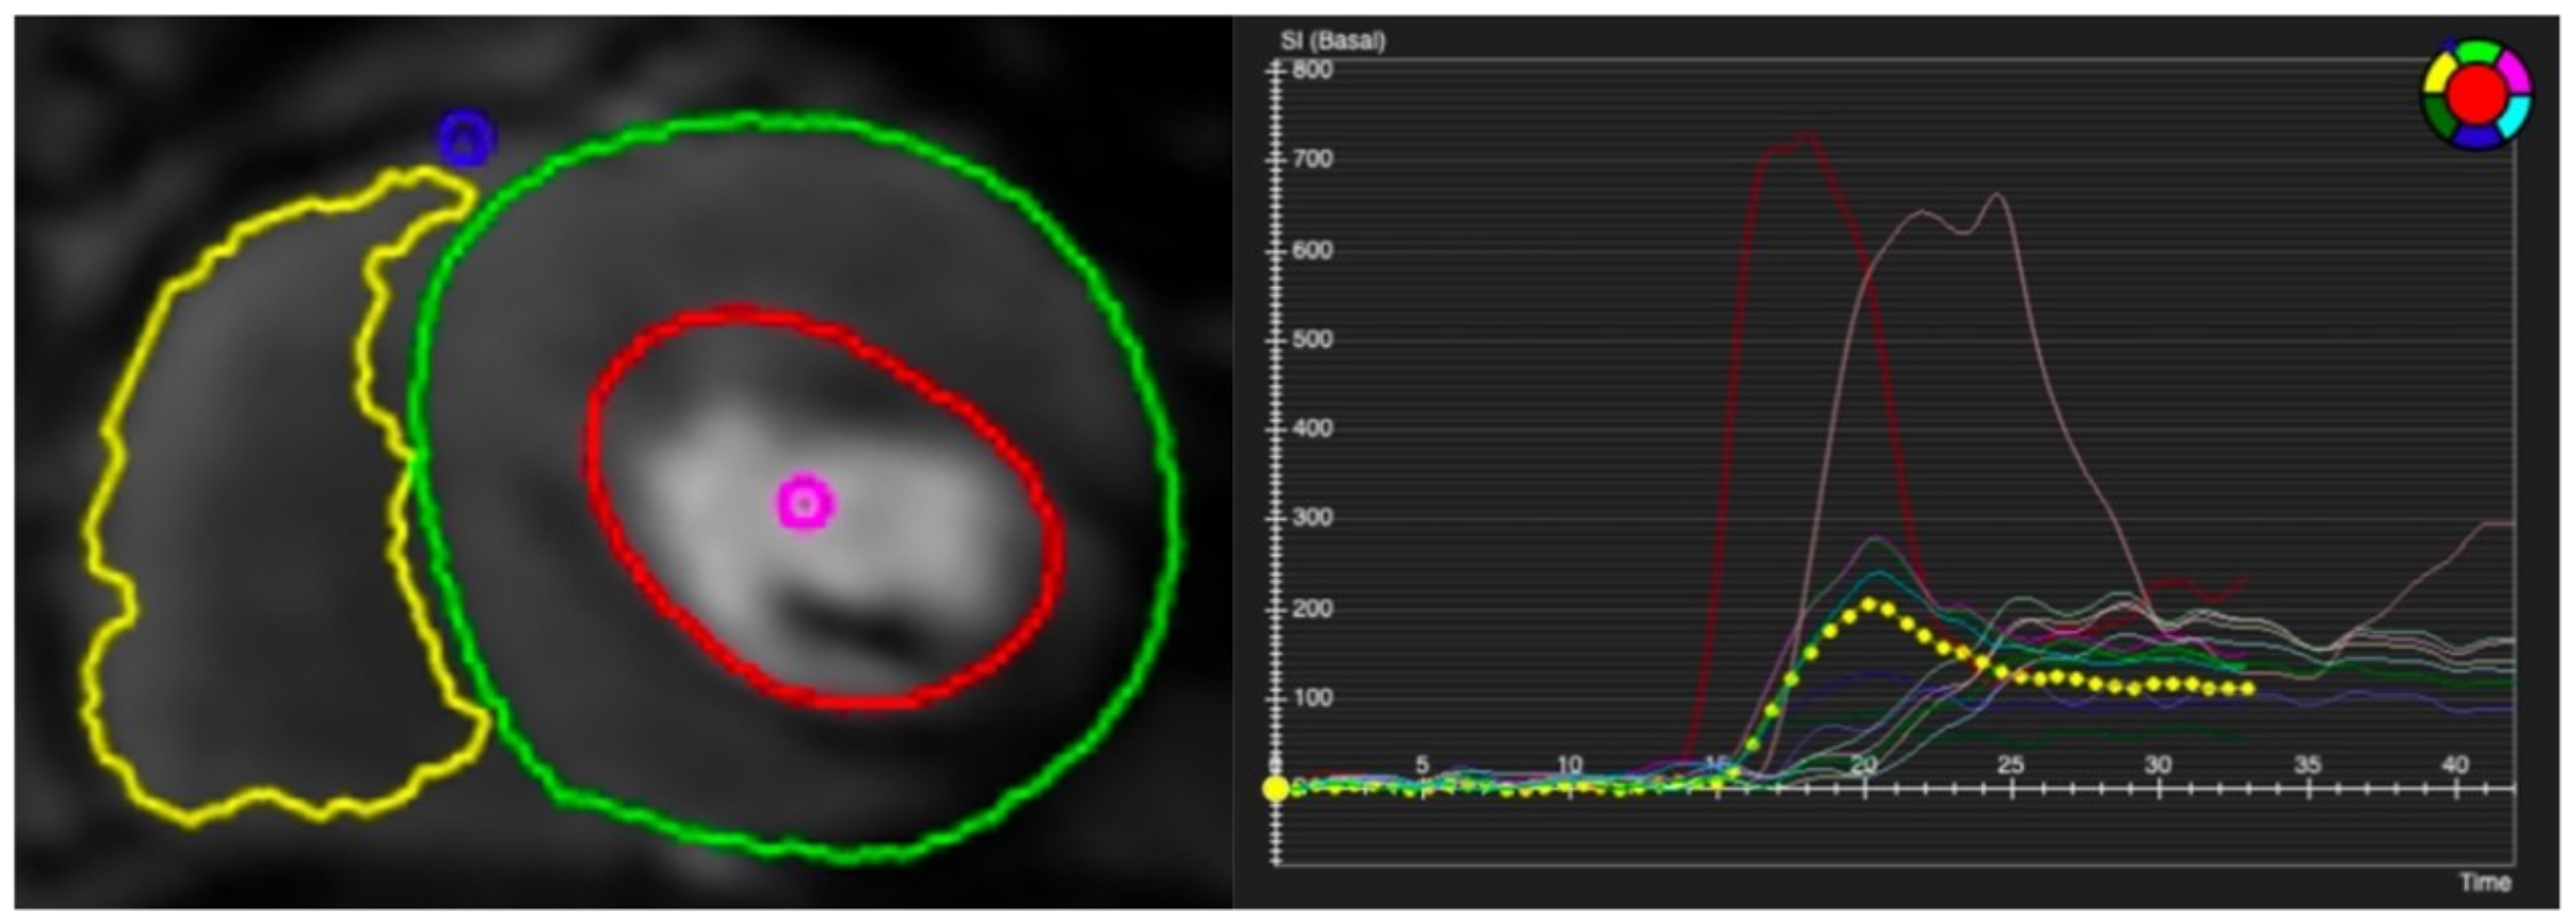

Visual assessment is subjective and highly dependent on expertise. Semi-quantitative and fully quantitative analysis of CMR perfusion based on signal intensity (SI) curves during the first pass of gadolinium contrast are solutions to this issue (Figure 5) [24]. Analysis methods that describe characteristics of the SI profile without estimating myocardial blood flow (MBF) are typically referred to as semi-quantitative analysis. The parameter calculated has been given various terms, such as the myocardial perfusion reserve (MPR) or the myocardial perfusion reserve index (MPRI) [20]. The calculation of these parameters has varied over time. For simplicity, we will refer to this as MPR, which is calculated as the ratio of MBF at peak stress and rest [25]. The MPR assesses the vasodilatory capability in response to vasodilator stress [26]. However, the MPR calculation and technique can result in different MPR values across scanners depending on how accurately the arterial input function (AIF) has been accounted for [27]. The accurate measurement of the arterial input function is an important requirement to quantify actual myocardial blood flow. To overcome the saturation or blunting of T1 signal intensity that prevents the precise measurement of the AIF, two methods have been utilised. One is a dual-bolus method [26], and the other is a dual-sequence technique [27].

Figure 5.

Contoured perfusion image (left) and signal intensity graph (right). Left panel demonstrates the contouring of right ventricle (yellow circle) and epicardium (green circle) and subendocardium (red circle) of left ventricle. Right panel shows the signal profile of each segment and blood pool.